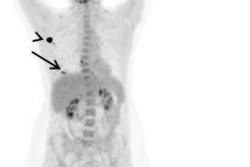

Editor's note: the PET image used to introduce this article on the homepage is of an 84-year-old woman with a multifocal cancer in the left breast and multiple bone FDG-avid metastatic lesions. Image courtesy of Surgical Oncology and Dr. Tima Davidson, Tel Aviv University, Israel.